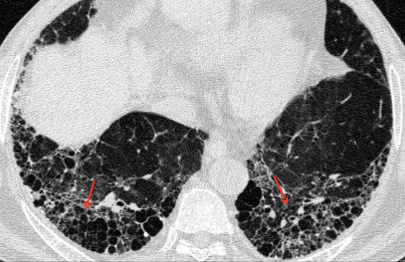

- Fleishner Society defines radiologic honeycombing as ‘clustered cystic air spaces, cysts of comparable diameters, and cyst diameters typically <10 mm surrounded by well-defined walls’. Honeycombing would present as pleural based rows of cysts stacked one upon the other, with the walls of the cysts in contact with each other (see figure below). These usually begin at the bases posteriorly but then will track anteriorly as well. You can read more on honeycombing at http://err.ersjournals.com/content/23/132/215.

- UIP pattern: This diagnosed when there are reticular opacities and honeycombing, with or without traction bronchiectasis. There should be a subpleural basal predominance with lack of the ‘inconsistent with UIP’ features. ‘Propeller blade” distribution pattern may be seen. This name is derived from the fact that the honeycombing or reticular changes move from being predominantly posterior to anterior as we move on sequential axial images from caudal to cranial. The diagnosis in these cases is unequivocally UIP.

UIP pattern. CT showing reticular opacities, traction bronchiectasis and honeycombing. (Image from Wikimedia Commons; contributed by Darel Heitkamp, MD.)